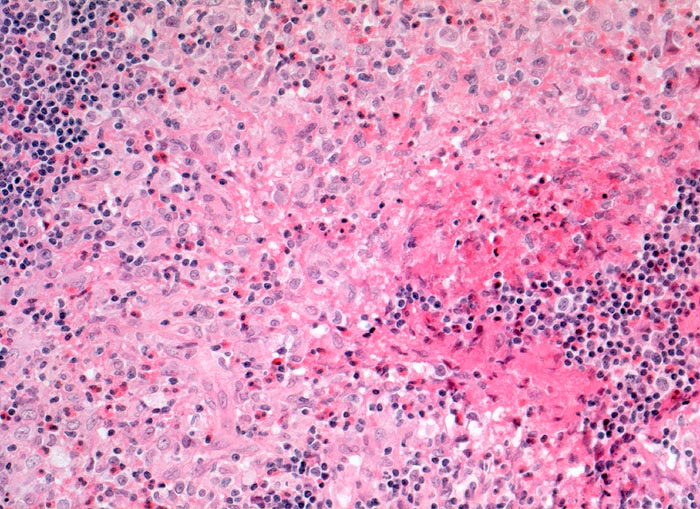

CD1a

CD1a wird von einer Reihe von Antigen-präsentierenden Zellen exprimiert. Unter anderem Langerhanszellen und interdigitierende Reticulumzellen. 70% aller Thymozyten sind CD1a positiv, nicht aber frühe Thymozyten oder ausgereiften Thymozyten

Reaktion in Neoplasien:

Precursor T-ALL positiv. Post thymische T-CLL, Sezary Syndrom, kutanes T-Zell Lymphom und nodale T-Zell Lymphome negativ.

Diagnostischer Nutzen:

Identifikation einer Langerhanszellhistiozytose.

CD1a ist positiv in kortikalen Thymomen.